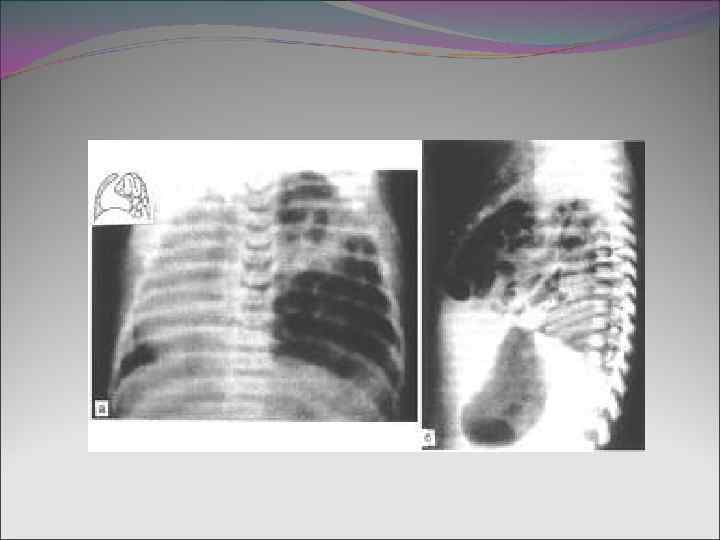

Диафрагмальная грыжа -Частота встречаемости 1: 2500 -1: 5000 новорожденных -Впервые патология описана в 1804 г. -Первые успешные операции по коррекции порока выполнены в 1940 г. -Несмотря на улучшения в диагнос тике и тактике ведения этой группы пациентов, летальность остается высокой в результате гипоплазии легких и сопутствующих пороков развития

-В 80% случаев возникает заднелатеральная грыжа Бохдалека, обычно левосторонняя (75%) -В 2% случаев грыжа возникает в переднем Отверстии Морганьи -В оставшихся случаях возникает параэзофагеальная грыжа -Грыжи Бохдалека–самые большие по размеру и ассоциированы с большей степенью гипоплазии легких

Патофизиология -Грыжевое содержимое вызывает смещение средостения, что приводит к гипоплазии противорасположенного легкого -При вдохе отсутствует сокращение диафрагмы, отрицательное давление в грудной полости способствует выпячиванию кишечного содержимого в грудную полость -Развивается легочная гипертензия из-за уменьшения количества легочных сосудов, утолщения мышечной стенки легочных сосудов (нереверсивные факторы), а также спазма мышечной стенки сосудов в ответ на гипоксию, гиперкапнию, ацидоз (реверсивные факторы) -Право-левый сброс через ОАП, ФОО при повышении давления в легочной артерии с дальнейшим усугублением гипоксемии -Главной причиной смерти является прогрессирующая гипоксемия и ацидоз

КЛИНИКА -Симптомы заболевания могут проявиться сразу после рождения или Спустя некоторое время -Начало и выраженность клинических проявлений отражает Степень гипоплазии легких, размер дефекта и объема абдоминального содержимого в грудной полости - Коррелирует с прогнозом заболевания † В течение 1 -го часа жизни –самая высокая смертность † После 6 -го часа жизни –как правило благоприятный исход - Классическая триада симптомов: цианоз, диспноэ, декстракардия -Запавший живот, выступающая грудная клетка, ослабление дыхания слева -Приглушенные или смещенные вправо тоны сердца -Перистальтические шумы при аускультации грудной клетки

ОБСЛЕДОВАНИЕ -Рентгенограмма органов грудной клетки с желудочным зондом -УЗИ сердца, брюшной полости, головного мозга для выявления сопуствующих пороков развития (пентада Кантреллаи др. )